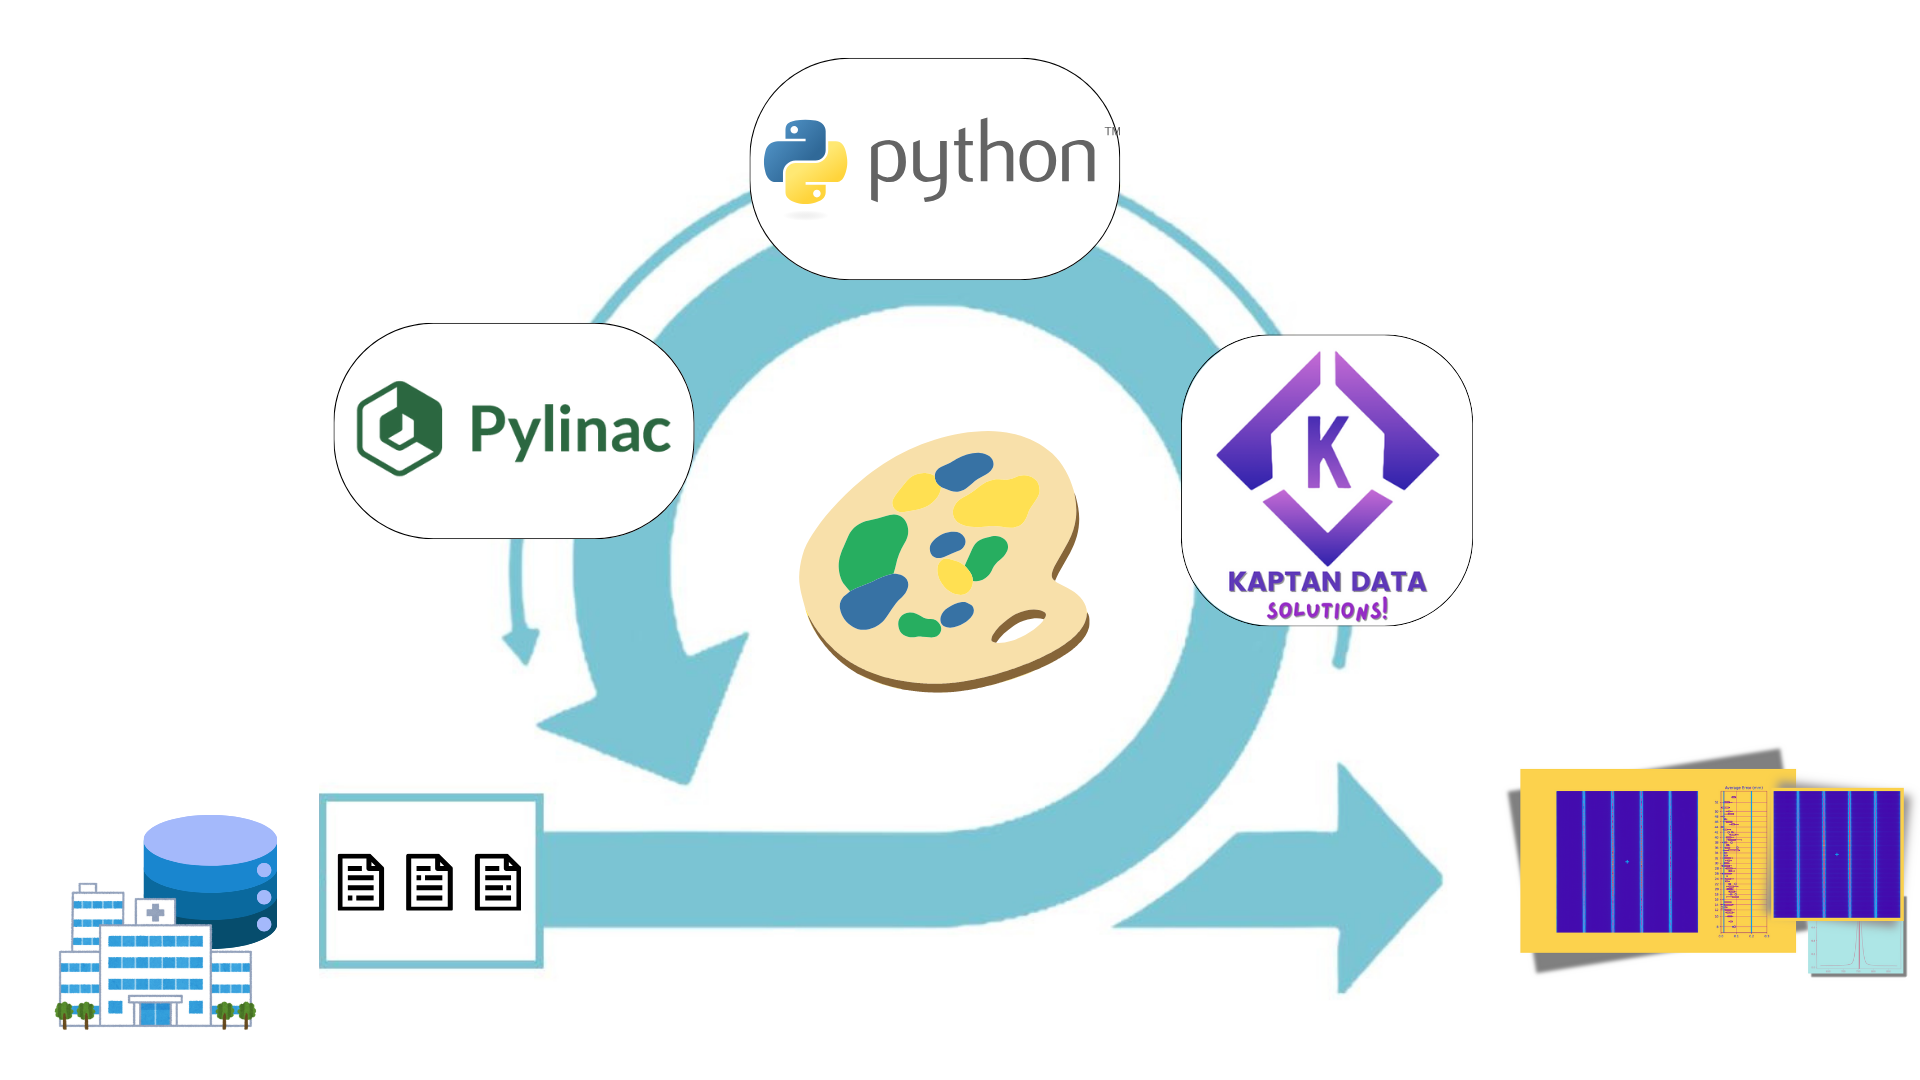

Enhance care with our medical Python Library Rt Dicom Monaco gallery of comprehensive galleries of therapeutic images. medically documenting photography, images, and pictures. designed to support medical professionals. Discover high-resolution Python Library Rt Dicom Monaco images optimized for various applications. Suitable for various applications including web design, social media, personal projects, and digital content creation All Python Library Rt Dicom Monaco images are available in high resolution with professional-grade quality, optimized for both digital and print applications, and include comprehensive metadata for easy organization and usage. Discover the perfect Python Library Rt Dicom Monaco images to enhance your visual communication needs. Our Python Library Rt Dicom Monaco database continuously expands with fresh, relevant content from skilled photographers. Instant download capabilities enable immediate access to chosen Python Library Rt Dicom Monaco images. Diverse style options within the Python Library Rt Dicom Monaco collection suit various aesthetic preferences. The Python Library Rt Dicom Monaco archive serves professionals, educators, and creatives across diverse industries. Regular updates keep the Python Library Rt Dicom Monaco collection current with contemporary trends and styles. Comprehensive tagging systems facilitate quick discovery of relevant Python Library Rt Dicom Monaco content. Time-saving browsing features help users locate ideal Python Library Rt Dicom Monaco images quickly.